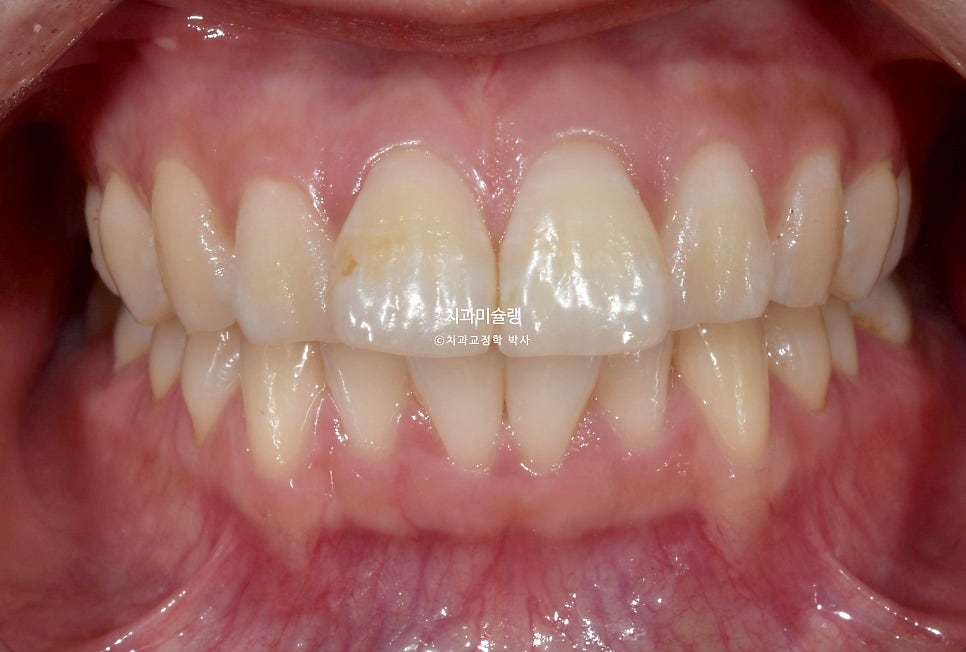

앞니 뻗침을 주소로 온 20대 환자분.

입술 돌출감은 못느끼나 앞니가 뻐드려져 있어 이 각도를 일자로 세우고 싶다는 이유로 교정치료를 받으러 오셨죠.

앞니 돌출 때문에 입이 편하게 안다물어지는 입술부전증이 경미하게 있습니다.

아래턱에 호두주름(자갈턱)이 생길정도로 심하지는 않지만 아랫입술에 돌출된 위 앞니가 걸쳐져 치아끝단이 살짝 보이는 정도 입니다.

입안을 보면 앞니가 뻗쳐있는 전형적인 돌출 입니다.

위아래 둘다 중절치가 특히 돌출되어 있습니다.